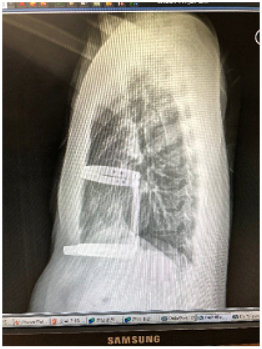

Figura 3 – Rx de tórax em perfil demonstrando as barras transversais que fixam duas barras metálicas. O sistema praticamente elimina a possibilidade de deslocamento das barras.